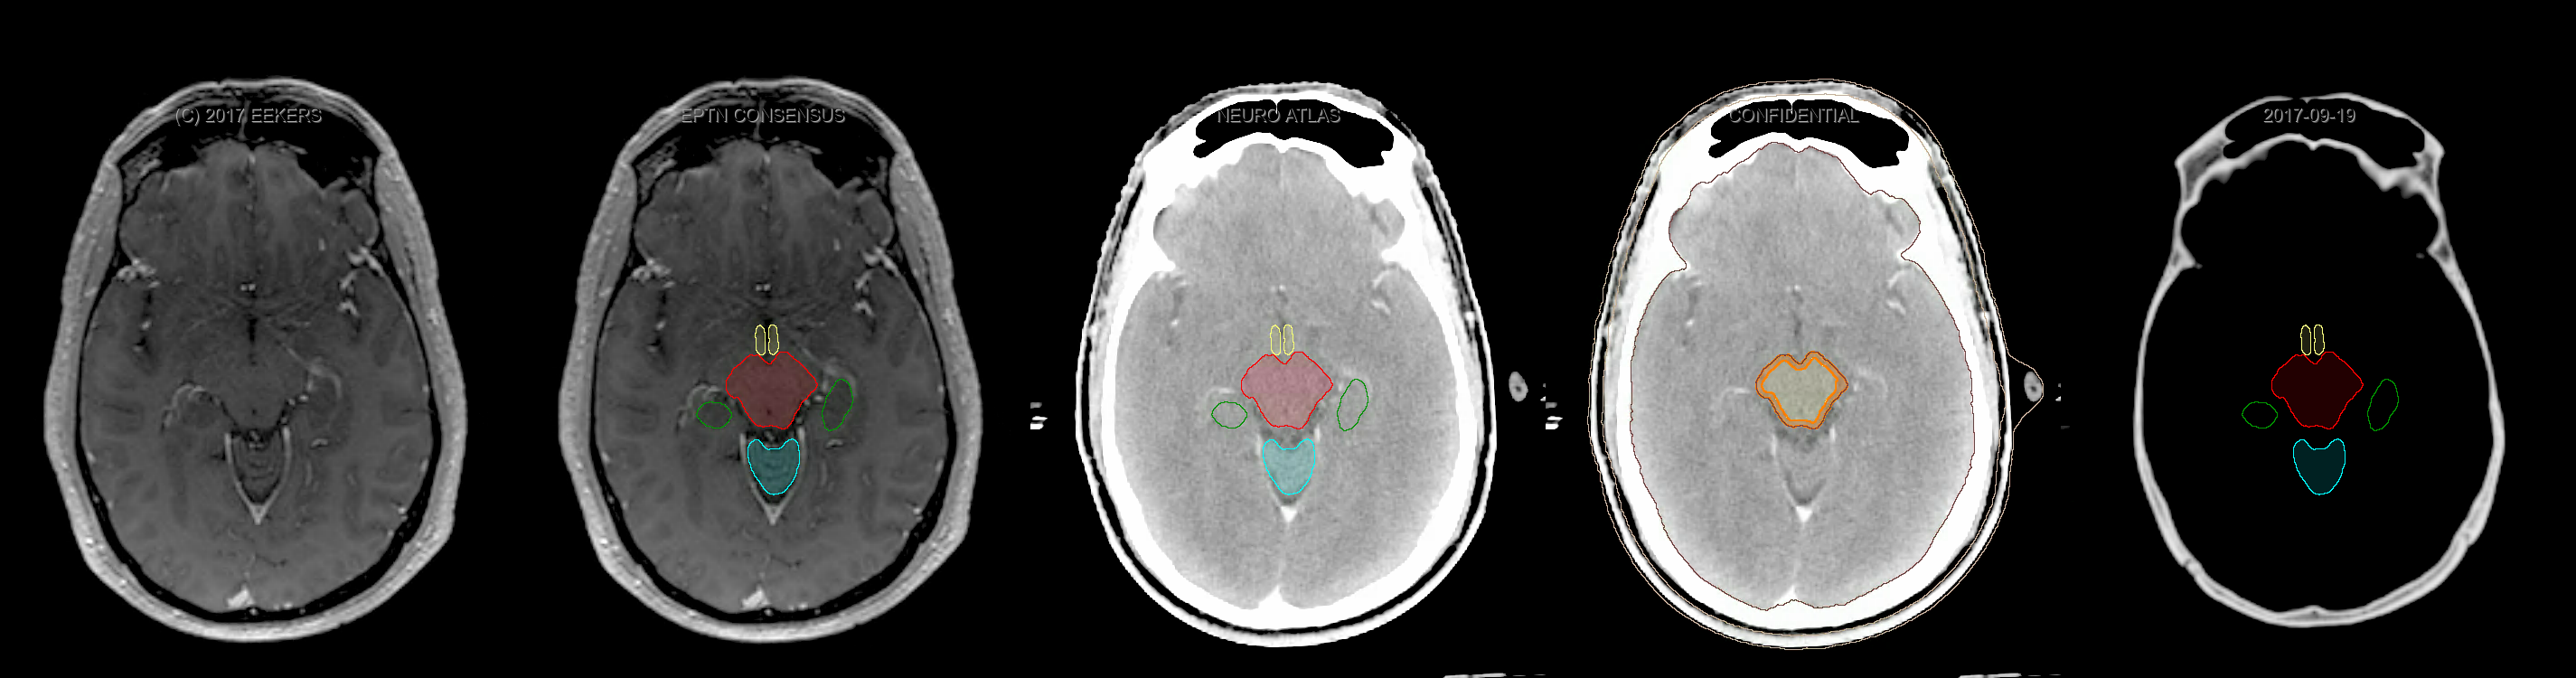

Eekers et al. have published an international neurological atlas for contouring of organs at risk in consensus with the European Particle Therapy Network (EPTN). The purpose of this consensus atlas is to decrease inter- and intra-observer variability in delineating OARs relevant for neuro-oncology. We propose this atlas is used in photon and particle therapy in order to derive consistent dosimetric data. When required this atlas will be updated according to new insights.

Included are all OARs known to be relevant for radiation-induced toxicity in neuro-oncology: brain, brainstem, cochlea, vestibulum & semicircular canals, cornea, lens, retina, lacrimal gland, optic nerve, chiasm, pituitary, hippocampus and skin. A new OAR relevant for neuro-cognition, the posterior cerebellum is also included.

Three-dimensional delineation of the fifteen consensus OARs for neuro-oncology are shown on CT and 3 Tesla (3T) MR images (slice thickness 1 mm with intravenous contrast agent). All are presented in transversal, sagittal and coronal view.

From left to right: MR without structures, MR with structures, CT (WW/WL 120/40) with structures, CT (WW/WL 120/40) with Brain and Brainstem Surface, CT (WW/WL 1500/120)with structures